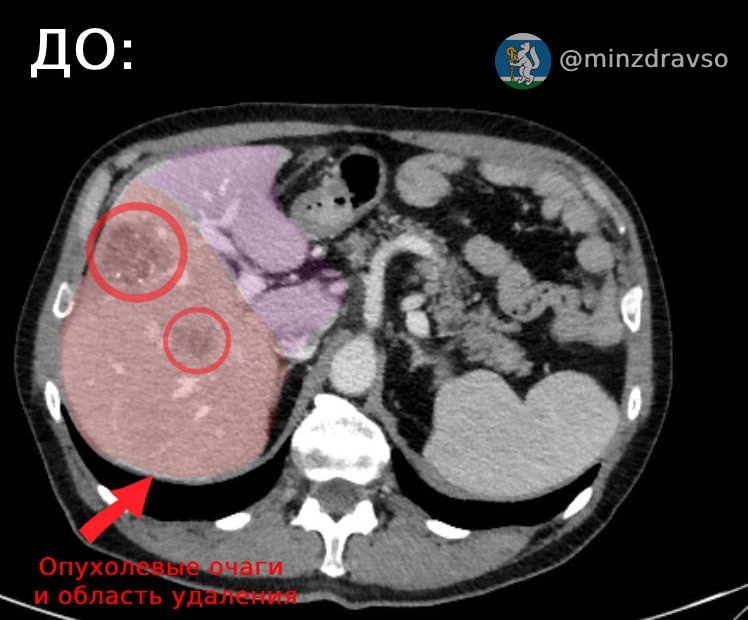

⚡️Специалисты Свердловского областного онкологического диспансера применили передовую методику лечения, чтобы помочь 60-летнему пациенту со злокачественным новообразованием печени.

У мужчины удалили почти 50% поражённого органа, при этом врачи закупорили ветви воротной вены, идущие к этой части печени, и помогли здоровым сегментам увеличиться в объёме.

🔴🟣На фото мы показали, насколько большое было поражение органа, которое требовалось удалить. И итоговую, "новую", печень.